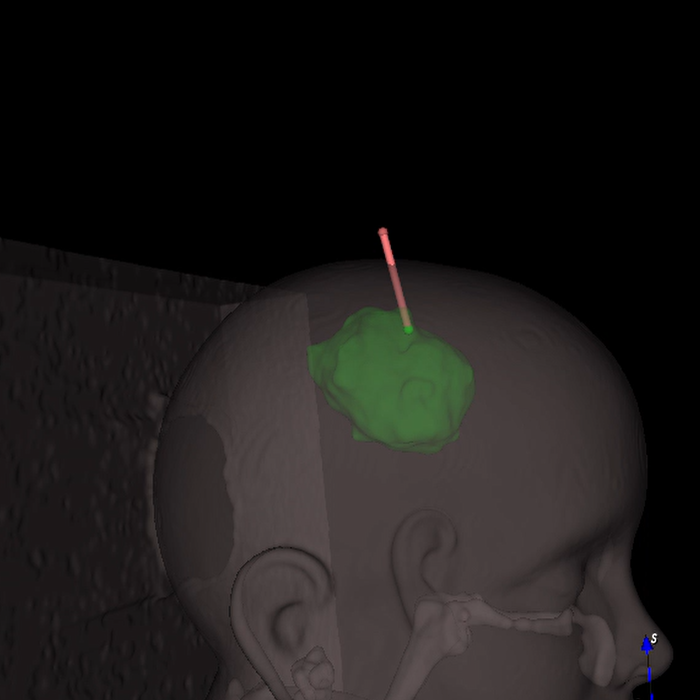

The user interface was custom designed to leverage the power of the software tools in a form which is intuitive and user friendly and provides the key clinical functionality. During the planning stage, for example, the user is walked through tasks such as skin segmentation, lesion and trajectory delineation, and landmark selection to be used for registration.

Pre-op Planning

Skin Segmentation

Target Segmentation

Trajectory Planning